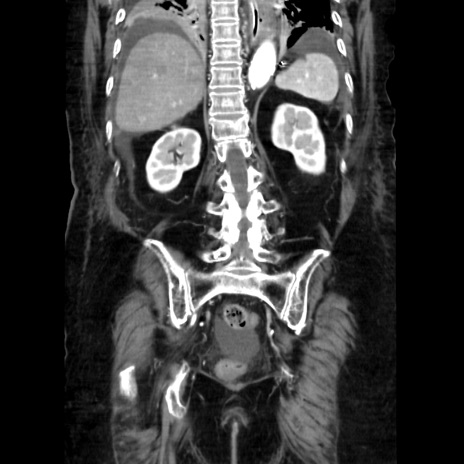

症例40(冠状断像)

【症例】90歳代女性

【主訴】腹痛・嘔吐

【現病歴】 食欲低下、嘔吐があり昨日他院受診。肺炎と診断され入院となる。入院後より腹部全体に圧痛あり。胃管留置され経過みていたが、症状持続するため、

当院転院となる。

【既往歴】胸椎圧迫骨折、胆石症

【身体所見】腹部:中央に激痛あり、圧痛あり、反跳痛不明

【データ】WBC 17100、CRP 18.82

冠状断像